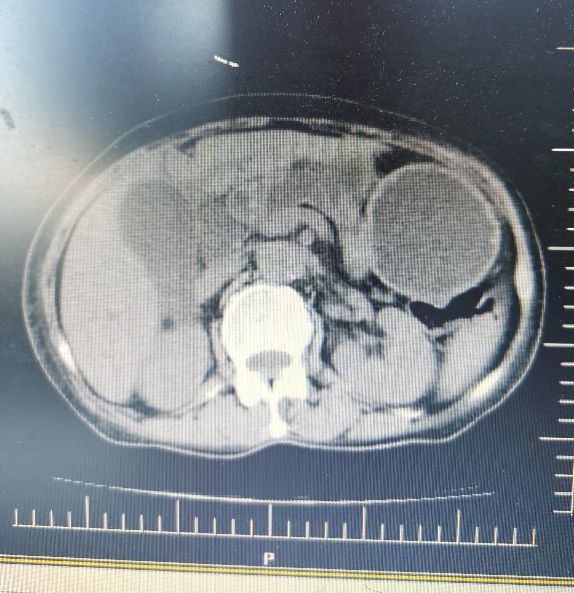

患者于10月8日来院进行第二疗程治疗。患者诉在家中时有上腹部疼痛,偶有发热,体温波动在37.5-38.5℃,食欲尚可,有时感体倦乏力。 血常规回报患者出现贫血,血红蛋白73g/L,肝功能胆红素及各项酶学指标均较前升高,腹部CT回报胰头病灶较前变化不明显,胆总管明显扩张,不除外低位胆道梗阻。

10月9日患者腹部CT